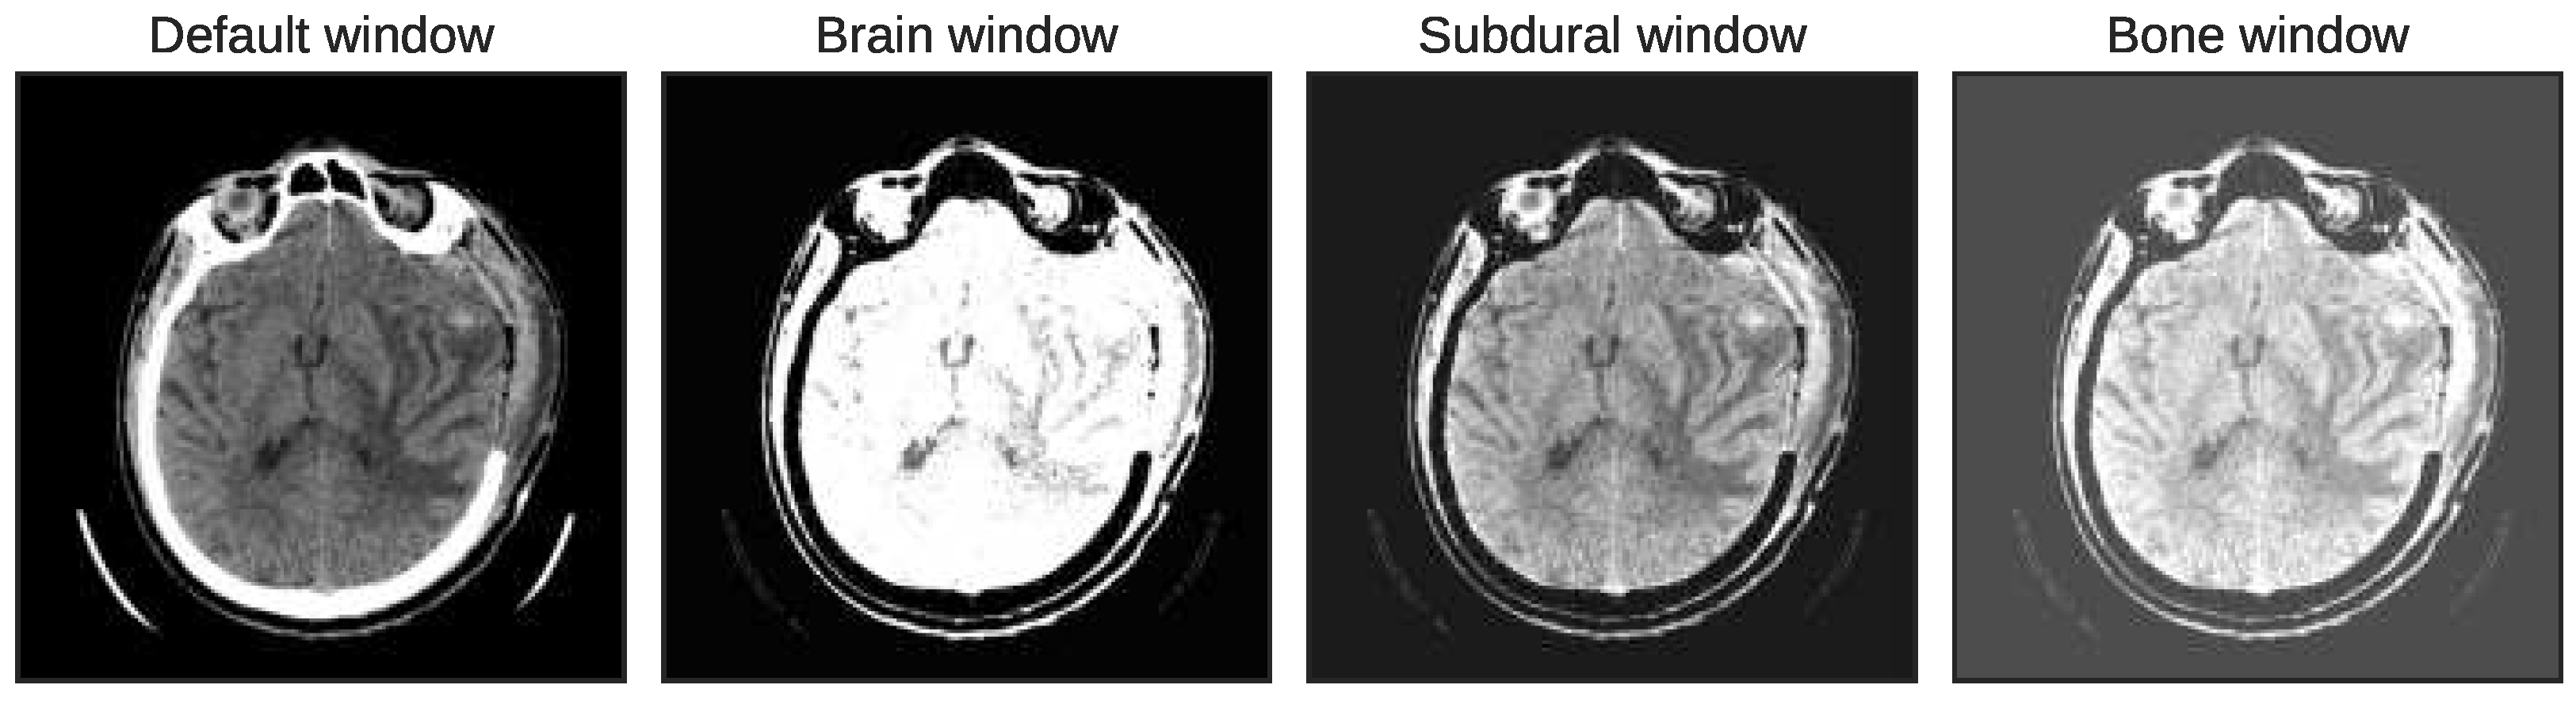

2.1.2. Multiwindowing and Adjacent Slicing